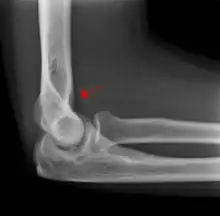

The fat pad sign, also known as the sail sign, is a potential finding on elbow radiography which suggests a fracture of one or more bones at the elbow. It is may indicate an occult fracture that is not directly visible. Its name derives from the fact that it has the shape of a spinnaker (sail).[1] It is caused by displacement of the fat pad around the elbow joint. Both anterior and posterior fat pad signs exist, and both can be found on the same X-ray.

In children, a posterior fat pad sign suggests a condylar fracture of the humerus. In adults it suggests a radial head fracture.

The fat pad sign is invaluable in assessing for the presence of an intra-articular fracture of the elbow. An anterior fat pad is often normal. However a posterior fat pad seen on a lateral x-ray of the elbow is always abnormal. The patient will be unable to flex their elbow and requires orthopaedic input.[2]

The posterior fat pad is normally pressed in the olecranon fossa by the triceps tendon, and hence invisible on lateral radiograph of the elbow.[3] When there is a fracture of the distal humerus, or other pathology involving the elbow joint, inflammation develops around the synovial membrane forcing the fat pad out of its normal physiologic resting place. This is visible as the "posterior fat pad sign" and is often the only visible marker of a fracture, particularly in the pediatrics population.